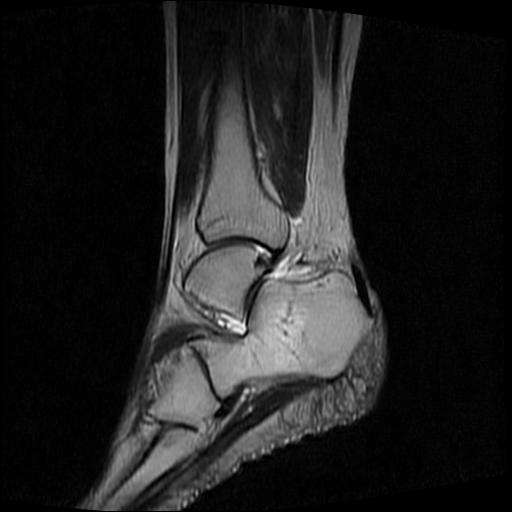

女性,70岁,右侧跟骨疼痛2个月,负重时加剧,不负重时不疼。

胫骨下段,跟骨、距骨可见斑片状异常信号区;考虑:转移瘤

跟骨病灶呈片状,边界模糊,可否考虑隐匿性骨折呢?

跟骨长t1长t2信号异常,边缘模糊(肿瘤一般边界清楚,故肿瘤不考虑),压脂像呈高信号--骨髓水肿(炎症?)。